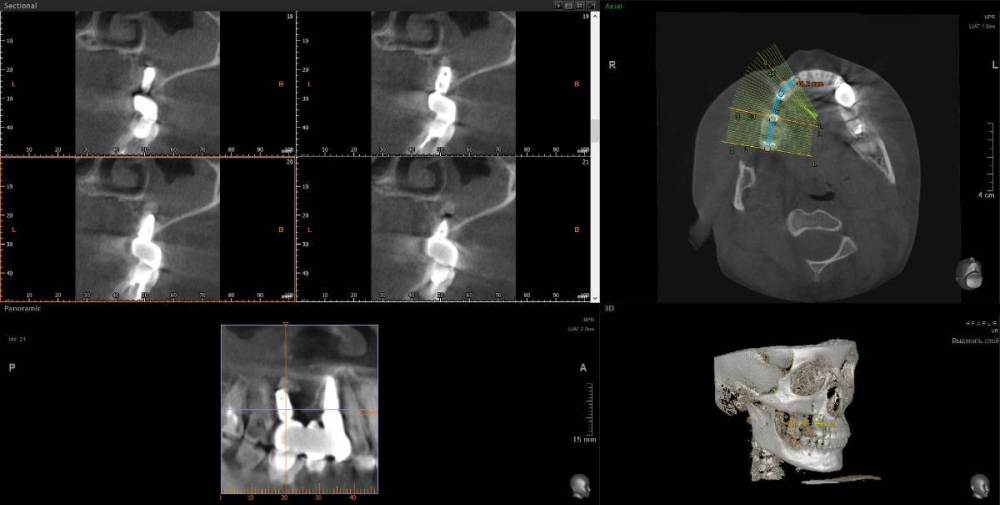

1. Из-за сильного воспаления верхнего зуба костная кость растворилась и дошло до пазух носа. Зуб рекомендуют удалить

2. Импланты установила 2 года назад, в итоге заплачено было 200 тыс. с учетом циркониевых коронок. На КТ обнаружилось сильное воспаление, как следствие растворилась костная ткань импланты, доктор сказал уже не спасти.

Буду очень признательна за консультацию - действительно ли нужно удалять зуб и импланты? КТ во вложении

IMHO. Зуб 18 стоит удалить, зуб 17 стоит полечить. Имплантат в позиции 16, похоже, придётся удалить, имплантат в позиции 14, на мой взгляд, вне опасности.